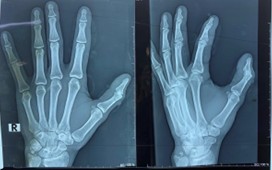

A 30-year-old right-hand-dominant male presented to the emergency department with a traumatic injury to the right thumb following an angle grinder accident. Examination revealed a deep laceration over the dorsal IP joint and complete loss of active extension. Radiographs confirmed an intra-articular fracture of the distal phalanx involving the IP joint, with minimal displacement and no subluxation.

Fig.1: Preoperative radiograph showing intra-articular fracture of the distal phalanx at the thumb IP joint.